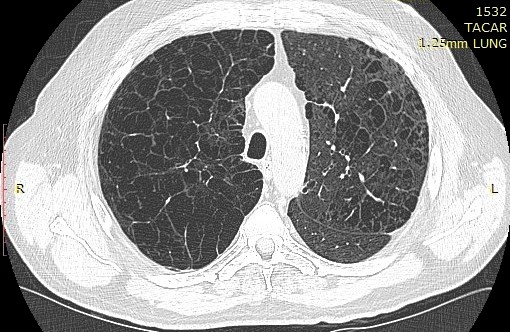

Presencia de enfisema por tomografía computada con espirometría normal

21 julio 2022

El enfisema a menudo está presente antes de que los resultados de la espirometría se vuelvan anormales, particularmente entre los hombres negros. Confiar únicamente en la espirometría para diferenciar la salud pulmonar de la enfermedad pulmonar puede resultar en un insuficiente reconocimiento del deterioro de la salud respiratoria. Annals of Internal Medicine, 19 de julio de 2022.